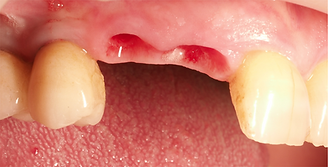

针对较大的口腔骨缺损

• 将CoreBone牙科骨粉与生理盐水或患者的血液混合。然后使用无菌器械(刮刀或刮勺)将混合物植入牙槽骨缺损处,压实后与周围组织紧密接触。

• 推荐使用可吸收生物膜覆盖本产品颗粒以促进新骨生长。